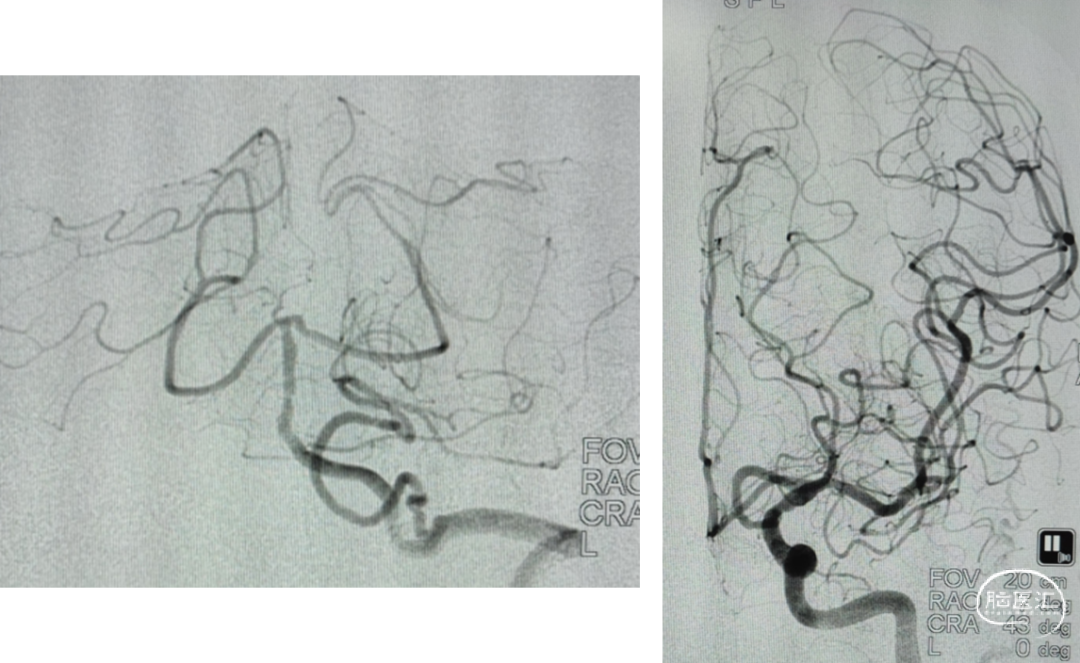

支架选择

LEO3.5x25 Atlas 3.0x15

工作位